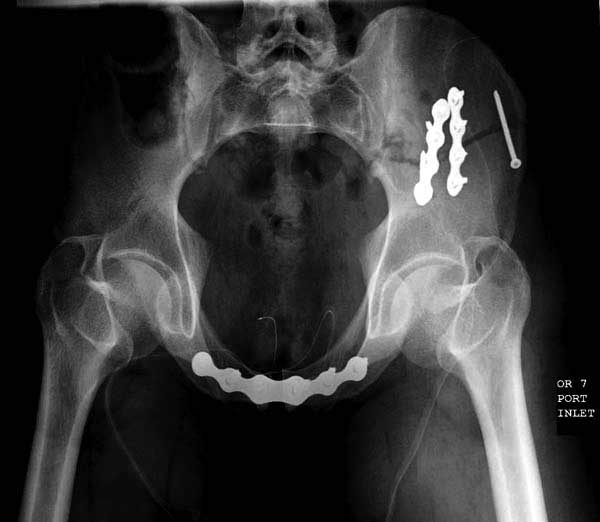

Здесь представлен случай 38 летнего больного (падение с высоты 9 метров) с нарушением тазового кольца. При поступлении для стабилизации передне-нижний аппарат наружной фиксации и на 6й день, вчера, операция из двух доступов.

Представлены снимки техники проведения стержней. Через место прикрепления прямой мышцы в Inferior Iliac Spine в направления вырезки создается жесткость. Weber clamp изнутри таза для репозиции, и фиксация после репозиции перелома крыла подвздошной кости. Наружный аппарат удален, нагрузка предполагается через два месяца.